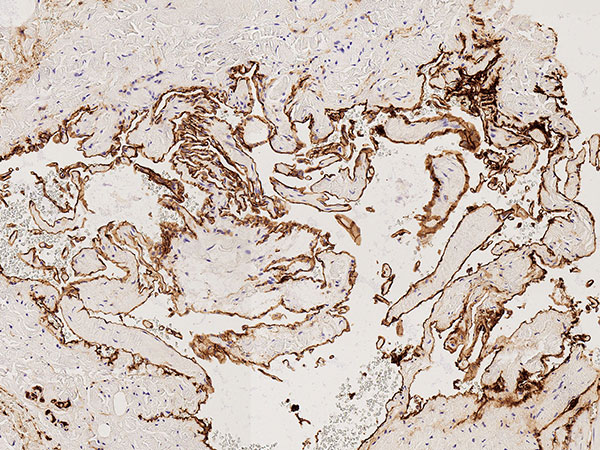

Histopathologie, D2-40-Färbung, 95-fache Vergrößerung: Die Gefäßendothelauskleidung der multiplen irregulären Gefäßräume färbt sich nicht mit Podoplanin (D2-40) an. Damit handelt es sich nicht um Lymphgefäßendothelien. In Zusammenschau mit dem Wandaufbau und der Form der Läsion ist dies damit ein weiterer klarer Hinweis auf eine venöse Malformation (keine lymphatische Malformation).